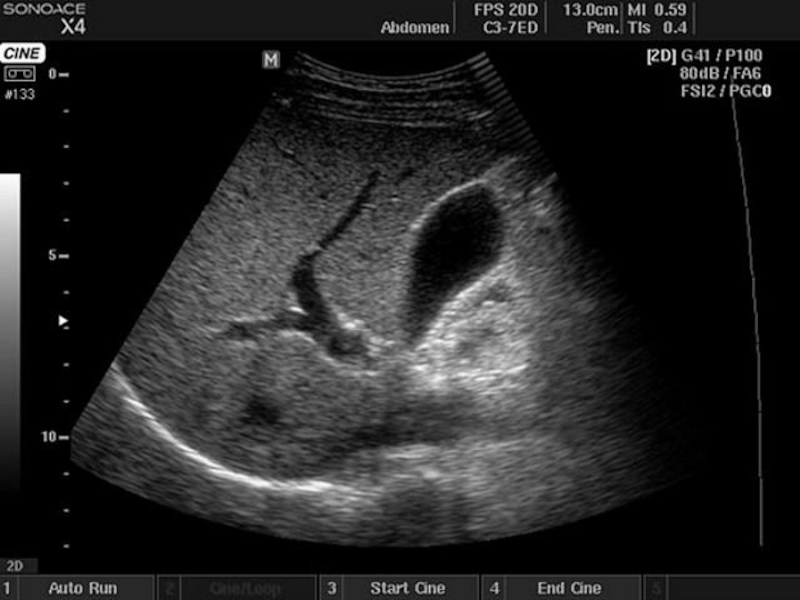

Слайд 12УЗИ желчного пузыря

исследуются аномалии развития пузыря и желчных протоков, диагностируется

желчекаменная болезнь, холециститы, полипы, доброкачественные и злокачественные опухоли.

УЗИ желчного пузыря исследуются аномалии развития пузыря и желчных протоков, диагностируется желчекаменная болезнь, холециститы, полипы, доброкачественные и злокачественные